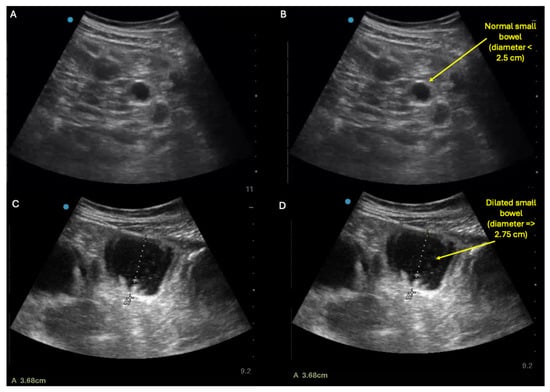

- Shokoohi, H.; Al Jalbout, N.; Peksa, G.D.; Mayes, K.D.; Becker, B.A.; Boniface, K.S.; Lahham, S.; Secko, M.; Chavoshzadeh, M.; Jang, T.; et al. Optimal bowel diameter thresholds for diagnosing small bowel obstruction and surgical intervention with point-of-care ultrasound. Am. J. Emerg. Med. 2024, 84, 1–6. [Google Scholar] [CrossRef]